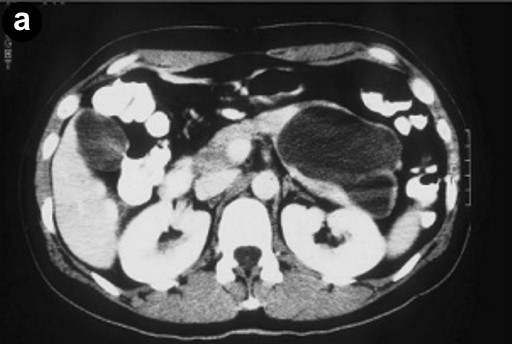

A 38-year-old woman with a previous diagnosis of ileal Crohn’s disease, presented to our institution complaining of epigastric discomfort, bloating, postprandial nausea and 2-3 bowel movements per day. She had no history of pancreatitis and an unremarkable gynecologic history. The patient was further investigated with abdominal ultrasonography and computerized scan tomography (CT) which revealed a large cystic mass (8.5 cm diameter) in the pancreatic tail (displacing the stomach wall) (Figure 1a). Fine needle-aspiration showed a mucinous content with detritus and acellular fluid. The patient underwent a distal pancreatectomy with splenectomy. No communication between the pancreatic mass and the lumen of the stomach was assessed. The postoperative course was uneventful. The patient remains free of symptoms 10 years after the procedure. Pathological study revealed a 9.5 cm diameter cystic mass with a homogeneous wall (Figure 1b). Part of the cyst was lined with gastric mucosa surrounded by a wall of muscularis propria well delineated from the normal pancreas tissue (Figure 2ab). A focal hyperplasia of simple cuboid epithelium and ciliated pseudostratified epithelium was observed (Figure 2cdef). The diagnosis of a gastric duplication cyst (foregut choristoma) of the pancreas was made.

Figure 1. a. Axial CT shows cystic tumor in the pancreas tail (8.5 cm diameter). b. Gross appearance of the cystic mass. The circumscribed lesion involves the tail of the pancreas. |